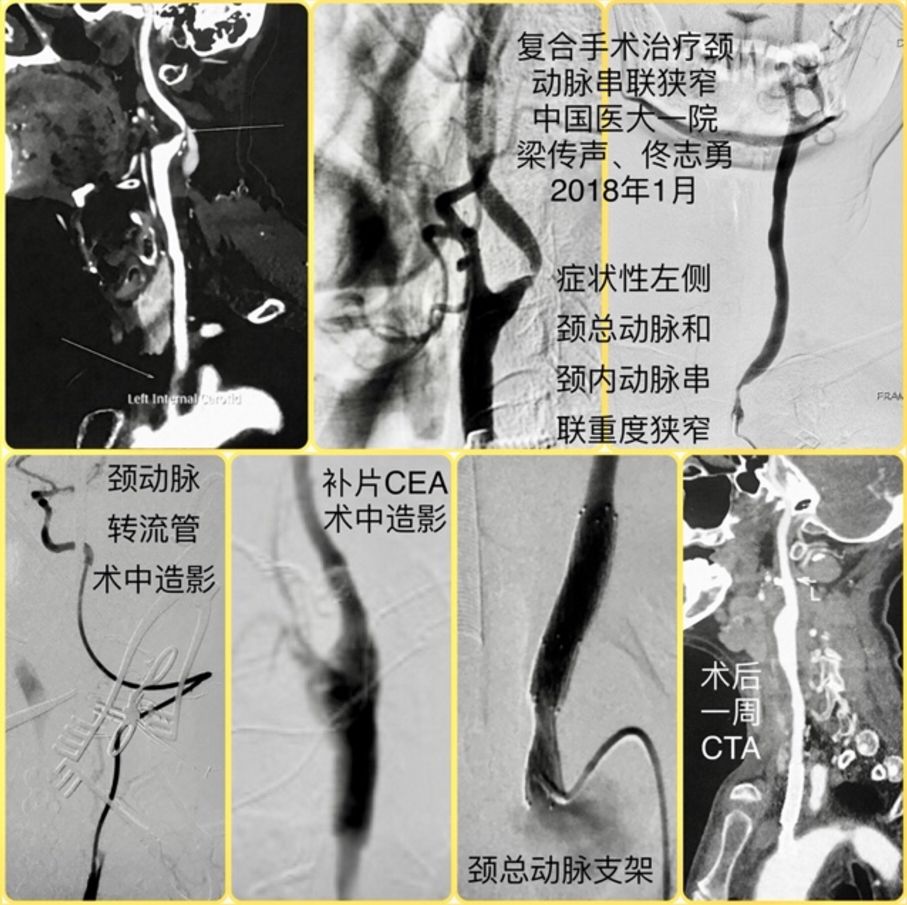

病例分享丨复合手术治疗左侧颈总动脉和颈内动脉串联重度狭窄一例